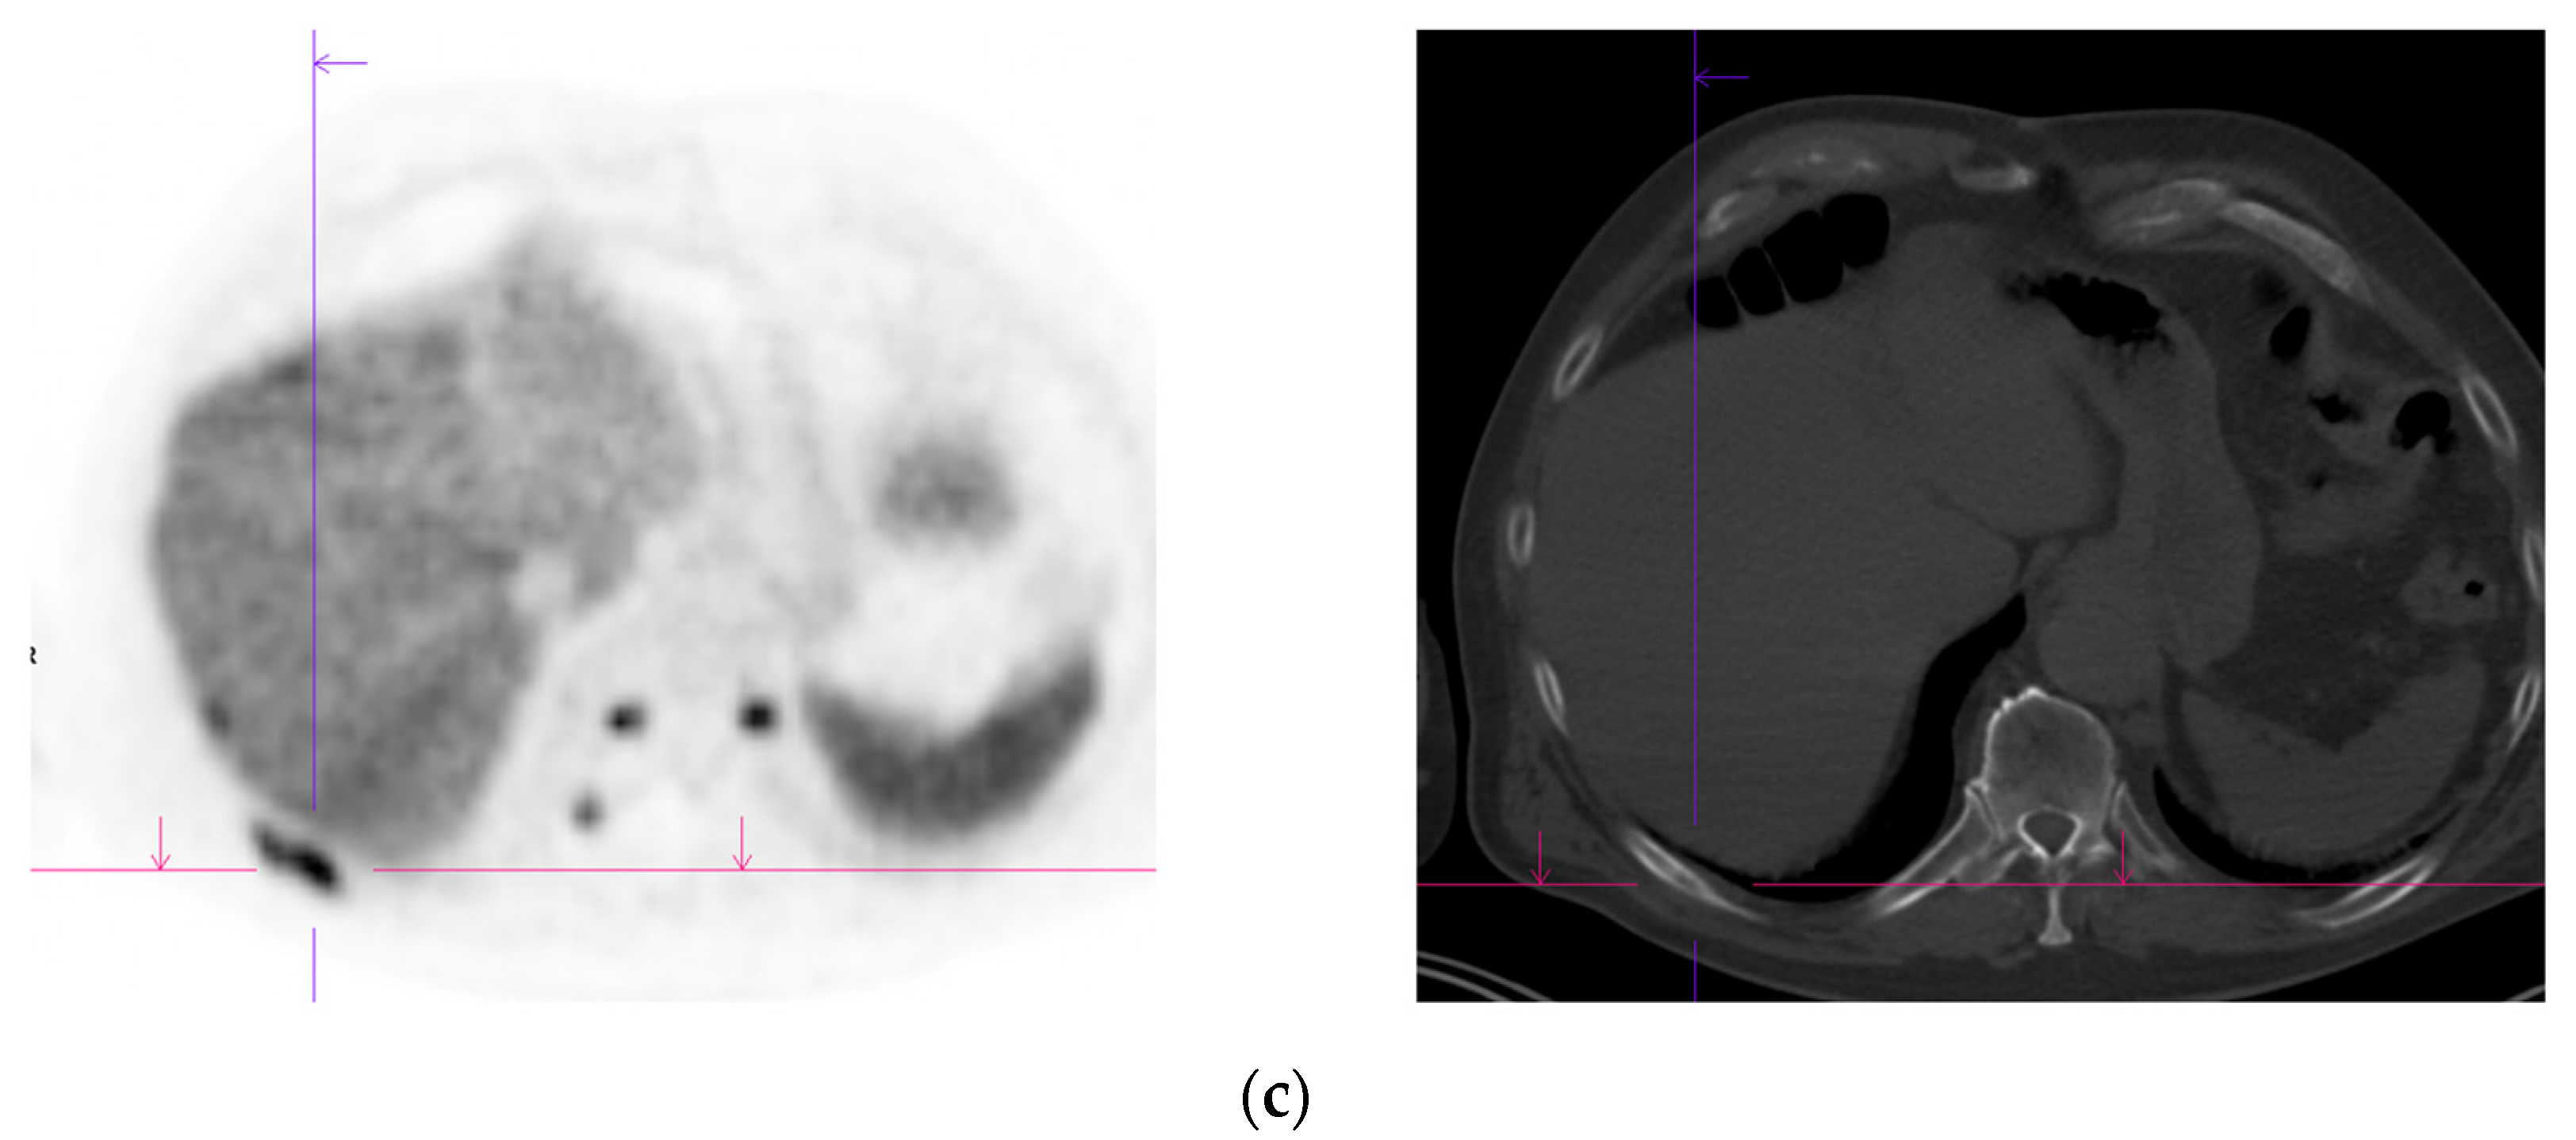

Figure 2.

Primary staging. 70 yr old M; PSA 42; Gleason 4 + 5 = 9; MR scan—PIRADS 6 at right apex; PIRADS 4 at left midzone. PSMA PET-CT: 68Ga-PSMA - 216 MBq; uptake 48 min; BMI = 30.5; Wt 83 Kg. (a): Coronal images—focal uptake midline apex anterior SUV = 26.1 with smaller focus SUV-5.4 right midzone; bulky disease in abdominal nodes; metastasis left humerus; left para-aortic node in thorax; bony metastasis left side of S1. (b,c): enlarged coronal and transaxial images of left common iliac/para-aortic nodal disease and uptake in apex of gland; transaxial images—node measures 14 mm SUV = 40.1; X-hairs show location. (d,e): enlarged coronal and transaxial images of right pelvic nodal that measures 1.4 mm SUV = 5.1; uptake in right midzone and apex as well as disease in left midzone of gland; X-hairs show location. (f,g): enlarged coronal images of para-aortic/para-oesophageal nodal disease in mediastinum; node measures 5.5 mm, SUV = 17.2; X-hairs show location.